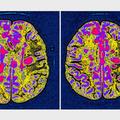

Estradnica je pri devetindvajsetih zbolela za multiplo sklerozo.

Hrvaška pevka Nika Antolos, članica banda Feminnem, je razkrila, da so ji pred dvema mesecema diagnosticirali multiplo sklerozo, o svoji borbi pa je spregovorila za IN Magazin, piše 24 Sata.

"Nog ne čutim več vse do popka, pred mesecem dni pa se je stanje še poslabšalo, sedaj ne vidim na levo oko. Vsi te simptomi, nemogoče jih je našteti. Boli me, vsak dan, utrujena sem, vrti se mi," je opisala Nika, ki pravi, da je njena prihodnost negotova: "Najbolj grozno od vsega je, da ne vem, ali bom pri devetindvajsetih sploh še živa, na vozičku, še naprej v bolečinah ali bo pri tridesetih veliko bolje. Pojma nimam. Moja malčica raste, moja malčica, a ji ne moram obljubiti ali bom z njo še dve leti."